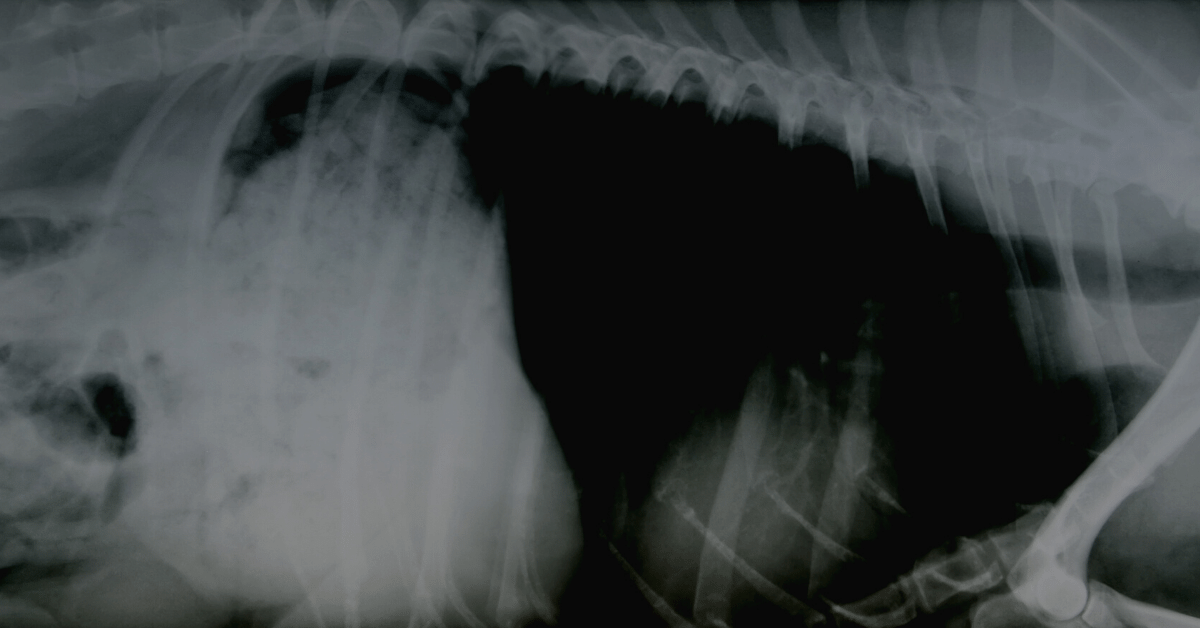

From newvetequipment.com

What Is an OverExposed XRay, and How to Avoid OverExposed Can Too Many X Rays Kill You Added exposures, from procedures such as medical imaging, can lead to an increase in our cancer risk. But many experts are concerned about an explosion in the use. Discuss with your doctor the risks and. But if you need numerous tests, you may wonder if you're getting too much radiation exposure and how it might affect you. With a 21. Can Too Many X Rays Kill You.